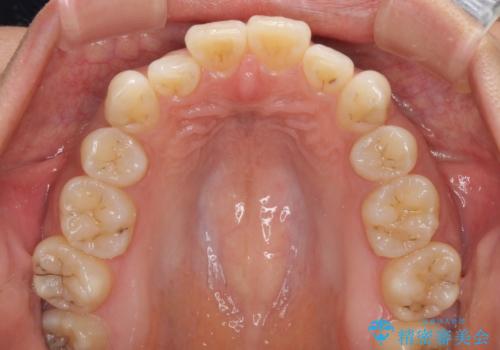

- 以前の矯正治療の後戻りにより、上下の前歯がでこぼこになってしまったことを気にして来院された患者様です。

口元がこれ以上突出することなく前歯の叢生が改善できるよう、歯と歯の間を削ってスペースを獲得し、インビザラインを用いて整えていくこととしました。

目安の装着時間である1日22時間をしっかりと実践してくださり、半年強という短期間で治療を終えることができました。